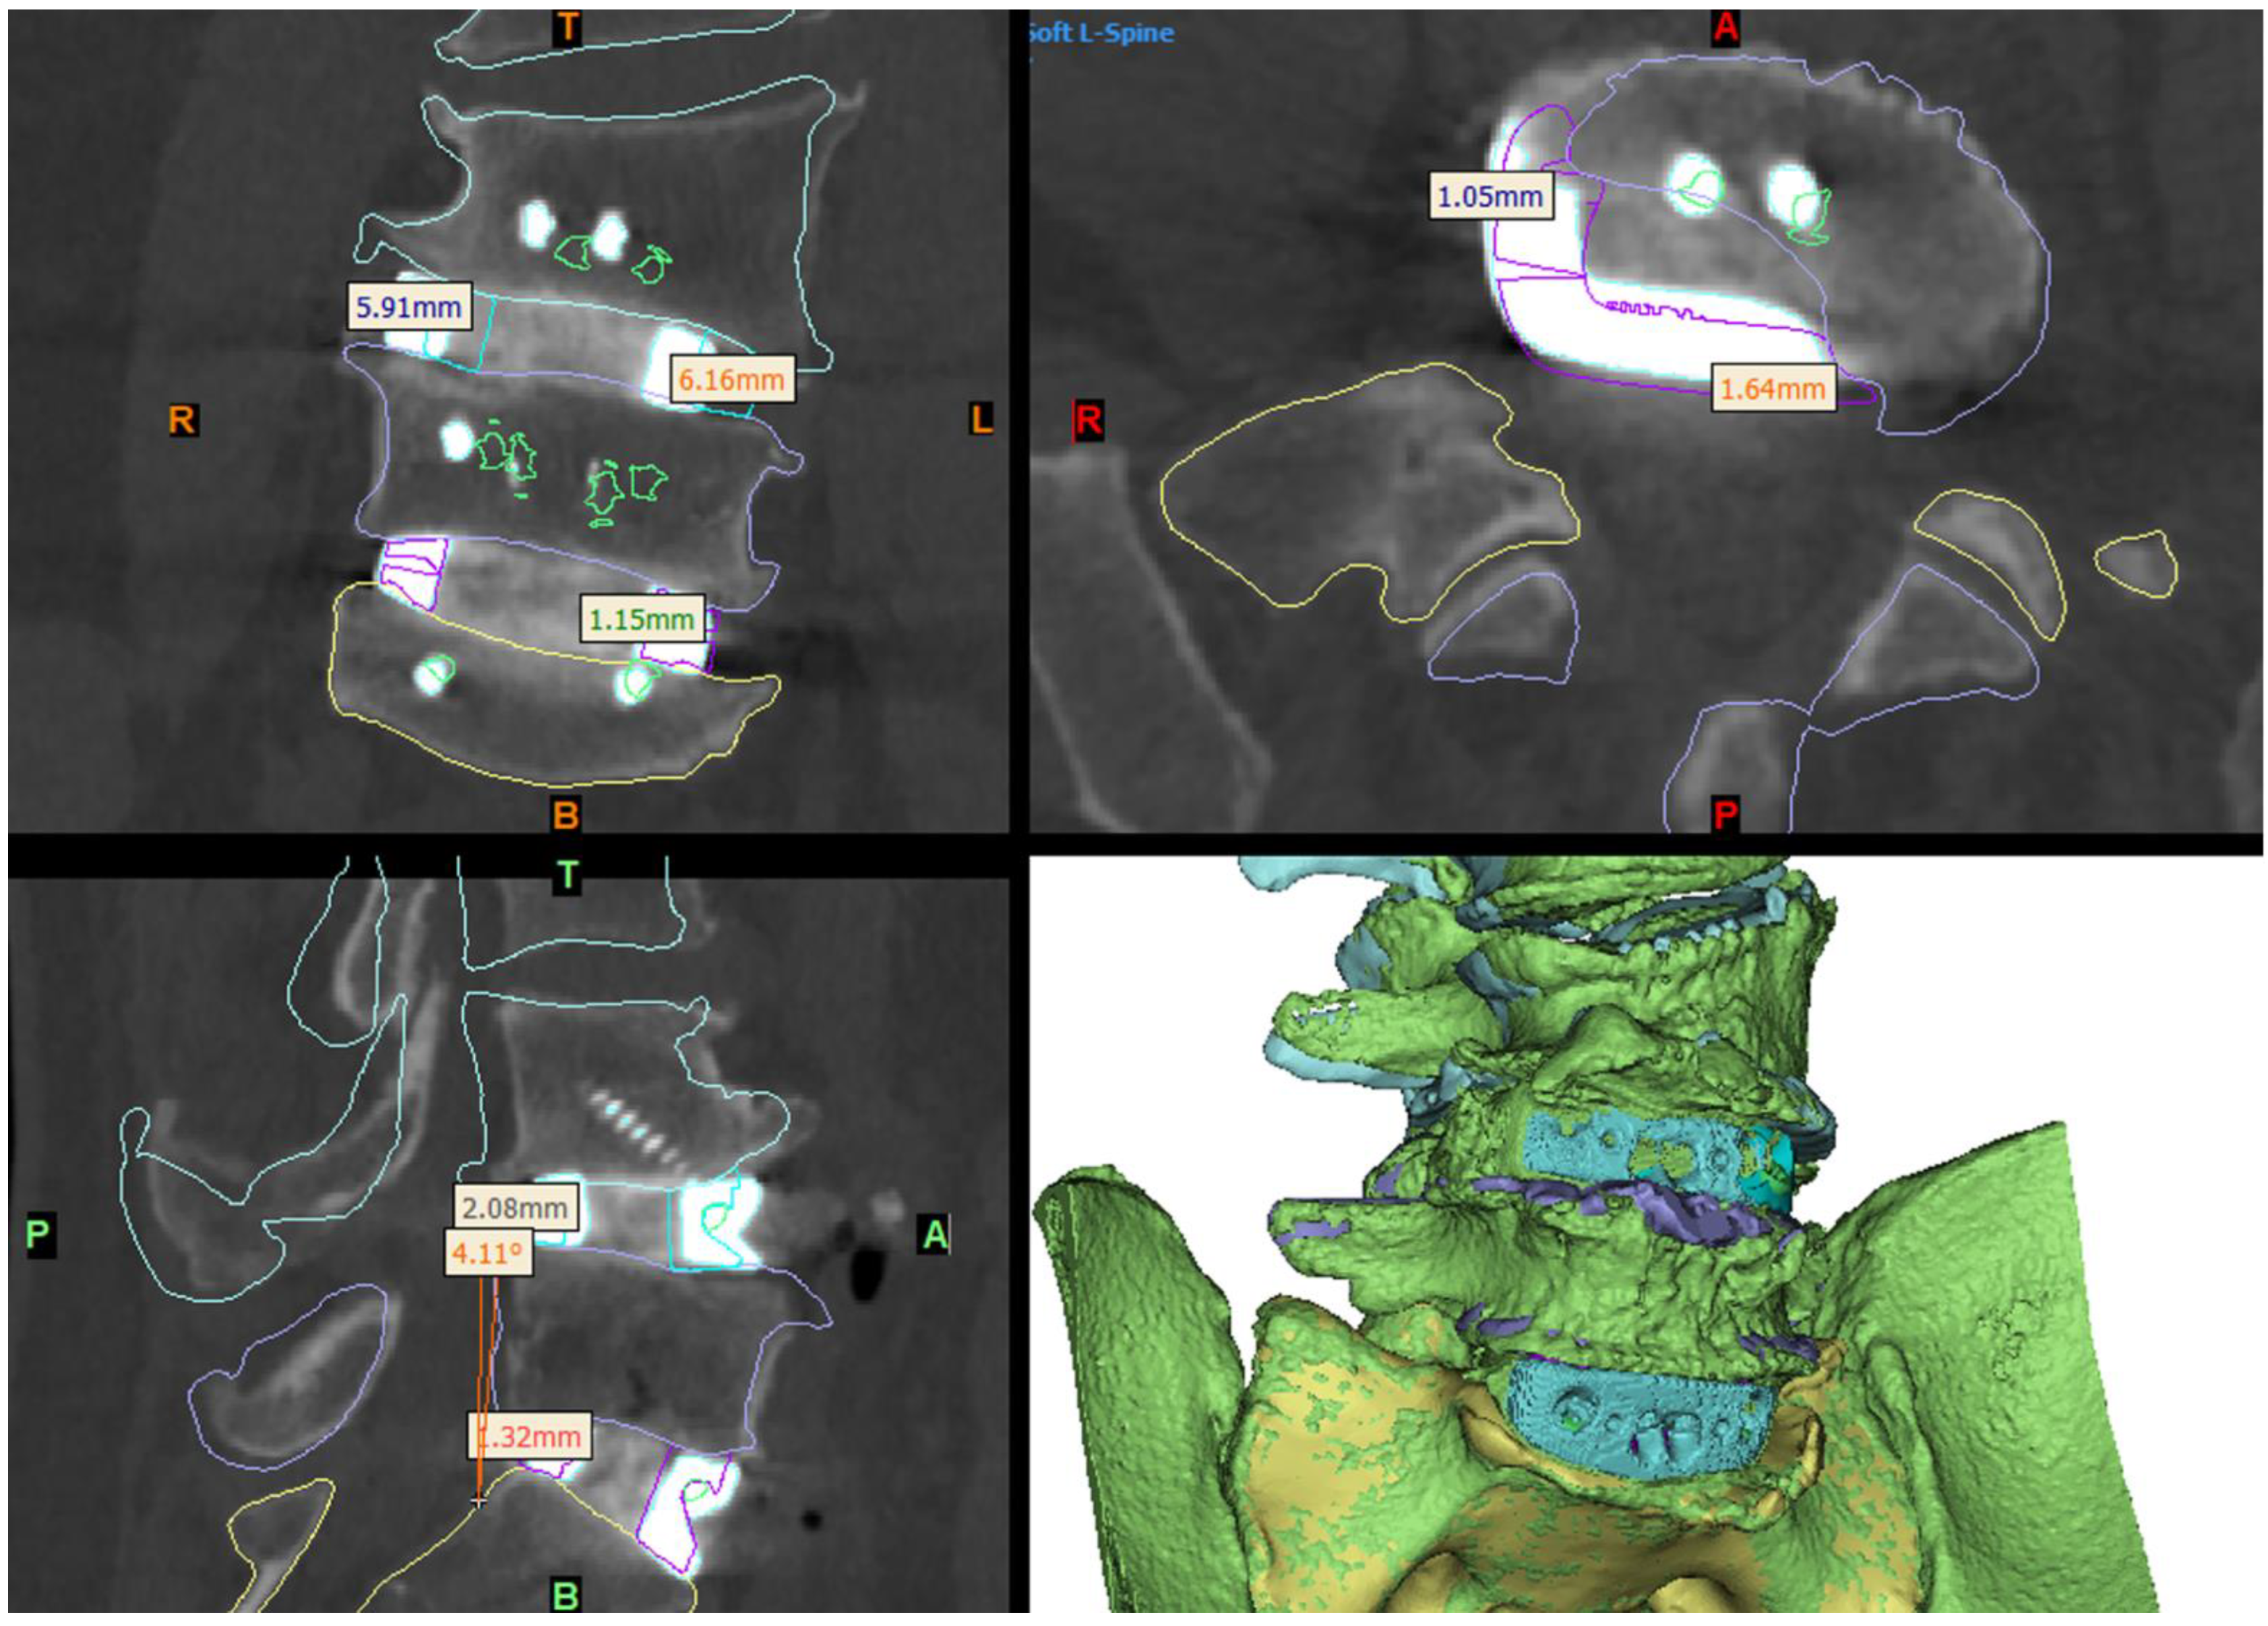

Figure 6.

Day-1 postoperative CT and 3D reconstruction of the construct (bottom right panel) compared to the virtual surgery planned (VSP) device and anatomy positioning (shown by the coloured outlines). The L5-S1 device was positioned very close to the VSP position, being ~1–1.5 mm further to the right and anterior than planned. The L4-L5 device was implanted ~6 mm to the left and ~2 mm anterior to the VSP position (see Section 3), which resulted in slightly less coronal and a sagittal-plane angle adjustment of the L4 hemivertebra being achieved than planned.

Imaging at day 1 postoperatively demonstrated excellent implant positioning (Figure 6). Disc and neuroforaminal height correction, as well as lordotic and partial scoliotic correction closely matched the planned correction in the VSP. At 9-month postoperative imaging, implant positioning and parameter corrections were stable. Early radiographic evidence of bony fusion at both operative levels and osteophyte resorption were appreciable (Figure 7).

The close adherence of the relative implant and anatomy positioning in postoperative imaging to the preoperative VSP demonstrates the accurate realisation of VSP correction goals and the validity of this technique (Figure 6). The ability to assess the vascular anatomy preoperatively and refer to the VSP intraoperatively allowed the surgical team to be better prepared, particularly in dealing with the extensive adhesions at the aortic bifurcation, and more rapidly successfully manage the intraoperative aortic tear [8]. The use of prominent osteophytes as patient-specific pathoanatomical landmarks also aided surgical navigation.